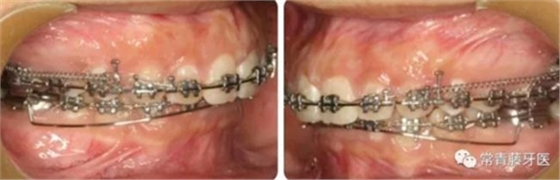

A67、B67之間植入微種植釘整體內(nèi)收上牙列,下頜配合多用途弓整平牙列改善覆合。

繼續(xù)內(nèi)收上牙列,此時下頜spee曲線基本整平。

與術(shù)前對比,術(shù)后可見前牙深覆合深覆蓋得到有效改善。